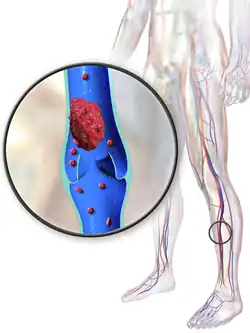

Deep vein thrombosis (DVT) is the formation of a blood clot in a deep vein, most commonly in the legs or pelvis.[8][lower-alpha 1] Symptoms can include pain, swelling, redness, and enlarged veins in the affected area, but some DVTs have no symptoms.[1] The most common life-threatening concern with DVT is the potential for a clot (or multiple clots) to detach, travel through the right side of the heart, and become stuck in arteries that supply blood to the lungs. This is called pulmonary embolism (PE). Both DVT and PE are considered as part of the same overall disease process, which is called venous thromboembolism (VTE). VTE can occur as an isolated DVT or as PE with or without DVT.[3] The most frequent long-term complication is post-thrombotic syndrome, which can cause pain, swelling, a sensation of heaviness, itching, and in severe cases, ulcers.[5] Also, recurrent VTE occurs in about 30% of those in the ten years following an initial VTE.[3]

DVT often develops in the calf veins and "grows" in the direction of venous flow, towards the heart.[74] When DVT does not grow, it can be cleared naturally and dissolved into the blood (fibrinolysis).[75] Veins in the leg or pelvis are most commonly affected,[8] including the popliteal vein (behind the knee), femoral vein (of the thigh), and iliac veins of the pelvis. Extensive lower-extremity DVT can even reach into the inferior vena cava (in the abdomen).[76] Upper extremity DVT most commonly affects the subclavian, axillary, and jugular veins.[11]